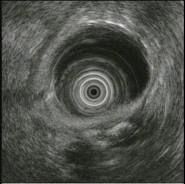

问题 女,55岁,腹痛便秘8年,大便干结伴排便不尽感,35天一次大便,无脓血便及恶心呕吐,食纳如常,体检无异常,结肠镜检查如图。患者哪种疾病可能性最大 ( )

选项 A、肠结核 B、溃疡性结肠炎 C、肠易激综合征 D、肠梗阻 E、结肠癌

答案 C